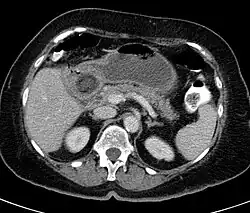

Hinweise auf die Ursache der Beschwerden geben verschiedene bildgebenden Verfahren. Oft gelangt mit Bildung der Fistel Luft in die Gallenwege, was in der Sonographie wie in der Computertomographie und gelegentlich auch schon in der Röntgenübersichtsaufnahme erkennbar ist. Bei einer solchen Aerobilie zusammen mit den Zeichen eines Dünndarmileus und dem Nachweis eines Gallensteins außerhalb der Gallenblase spricht man von der für einen Gallensteinileus typischen Rigler-Trias. Allerdings liegt beim Bouveret-Syndrom der Verschluss unmittelbar am Magenausgang so hoch, dass Zeichen des Dünndarmileus fehlen können. Die Laborwerte sprechen für eine Entzündung und eventuell Elektrolytstörungen.